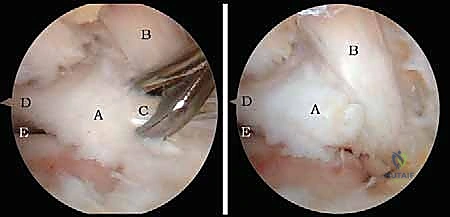

* استئصال العظم الزائد (Os Trigonum Excision): يتم فصل العظم الزائد بحذر عن الأنسجة المحيطة واستخراجه بالكامل، مما يزيل سبب الانحشار والألم فوراً.

* تحرير وتنظيف وتر (FHL): إذا كان الوتر ملتهباً ومحاصراً، يتم قطع سقف النفق الليفي لتحريره، وإزالة الأنسجة الملتهبة (Tenosynovectomy) لضمان انزلاقه بحرية.

* إزالة الأجسام الحرة والنتوءات العظمية: يتم التقاط الشظايا العظمية أو الغضروفية وإخراجها، واستخدام أدوات دقيقة (Burr) لتنعيم النتوءات العظمية التي تسبب الاحتكاك.

* معالجة الغضاريف: تنظيف الآفات الغضروفية وتحفيز النخاع العظمي (Microfracture) لتكوين غضروف ليفي جديد.

الخطوة 3: الاستكشاف البانورامي (Diagnostic Arthroscopy)

يتم إدخال كاميرا المنظار عالية الدقة (4K) عبر أحد المداخل، بينما تُستخدم الأدوات الجراحية الدقيقة في المدخل الآخر. تتيح الكاميرا للدكتور هطيف رؤية الهياكل الداخلية مكبرة عشرات المرات على شاشة عملاقة، مما يسمح بتقييم دقيق للمفاصل، الأوتار، والأربطة.